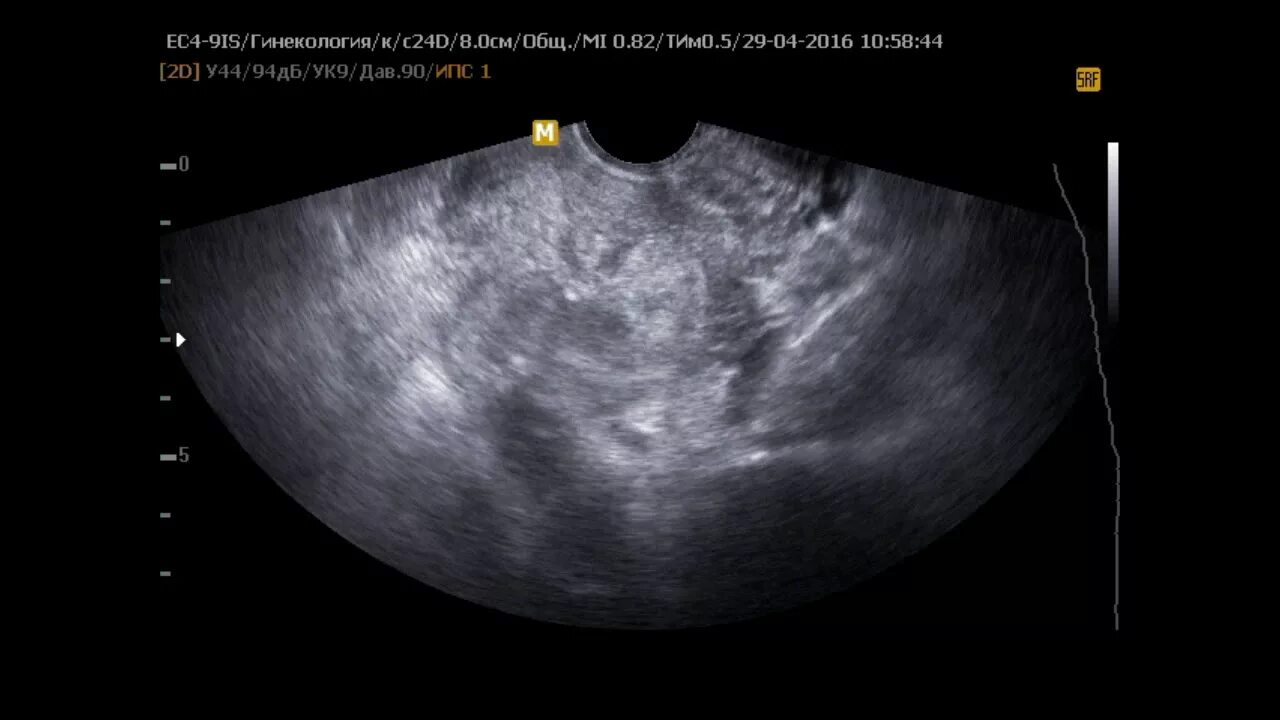

Нужно ли удалять миому матки